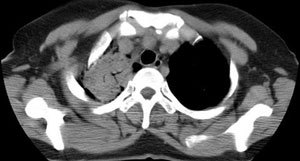

女性,30岁。

病史为胸痛20多天,无畏寒发热,无消瘦,无咳嗽咳痰。总之症状很逍遥。

临床以胸痛待查收住入院。

双肺野可见散在大小不等结节及肿块影,内密度不均匀,边缘部分清,部分欠清,纵隔未见明显肿大淋巴结.右侧胸腔少理积液.结合临床,考虑韦格肉芽肿可能吧,巨淋巴增生,结节病,特殊感染都要考虑.转移瘤临床不象.

本病例特点如下:

1.青年女性,以胸痛20多天就诊,无呼吸道及感染临床症状体征,无原发肿瘤病史;

2.肺ct表现为两肺多发大小不等结节影,大结节位于肺尖部,小结节多位于肺外带胸膜下,大结节内可见支气管充气征,周围可见月晕征(指在结节状或肉芽肿样病灶周围呈环形磨玻璃影),右肺门及腔静脉后可见小淋巴结,右侧胸腔内少量液体。

两肺散在分布大小不等的肿块及结节影,边缘毛糙,有分叶、毛刺,病灶密度不均匀,可见支气管充气相与空泡征。病变大多位于胸膜下,可见胸膜凹陷及胸腔积液。气管腔静脉间可见小结节影。